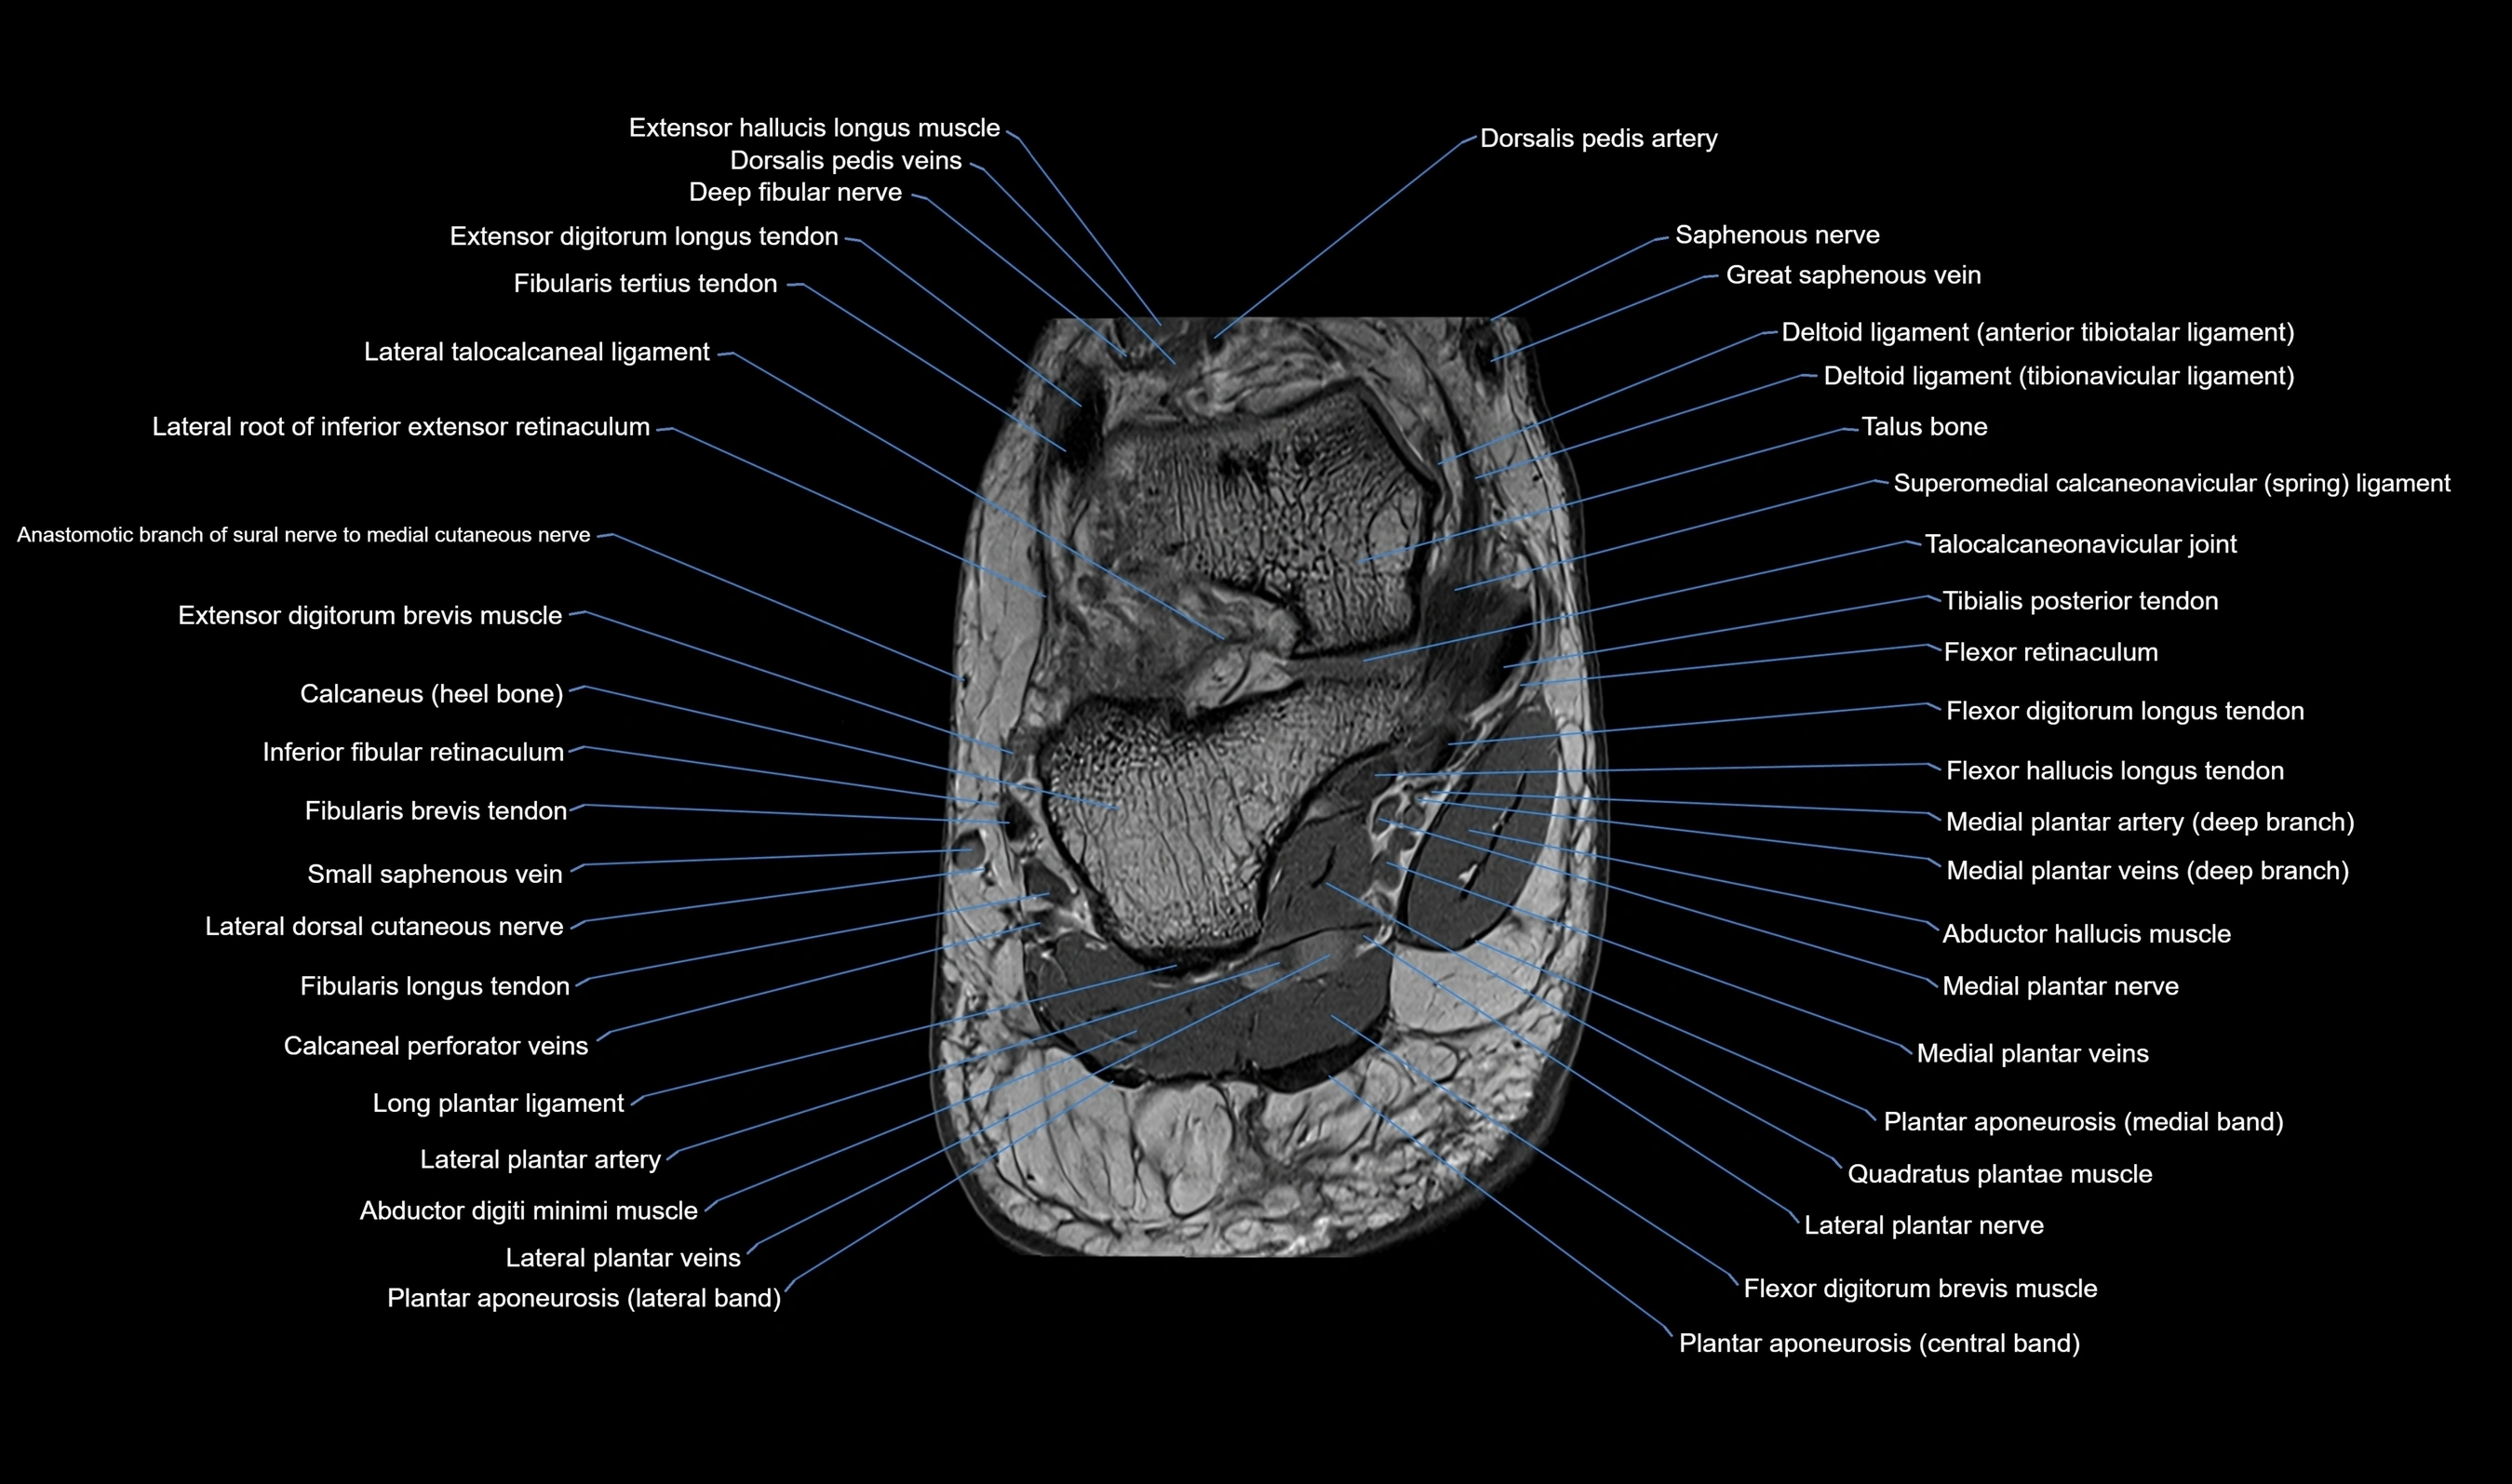

MRI image